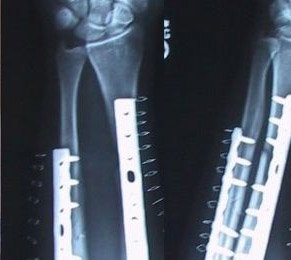

Der Unfall - ist meist schneller passiert als man denkt...